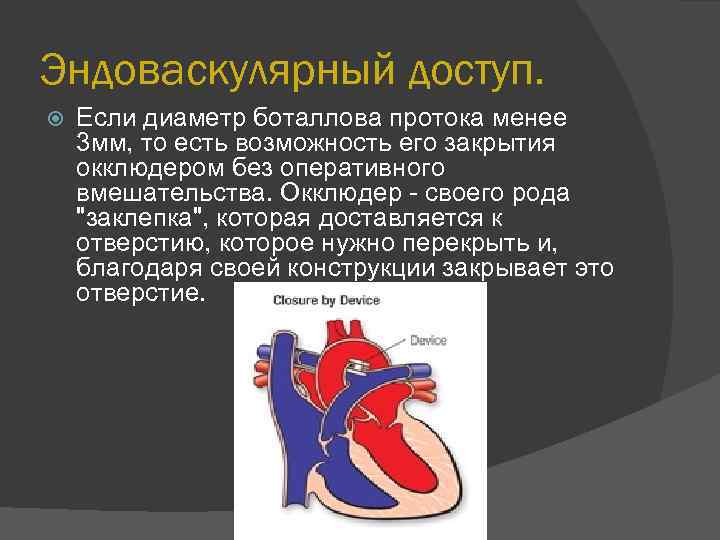

Эндоваскулярный доступ. Если диаметр боталлова протока менее 3 мм, то есть возможность его закрытия окклюдером без оперативного вмешательства. Окклюдер - своего рода "заклепка", которая доставляется к отверстию, которое нужно перекрыть и, благодаря своей конструкции закрывает это отверстие.